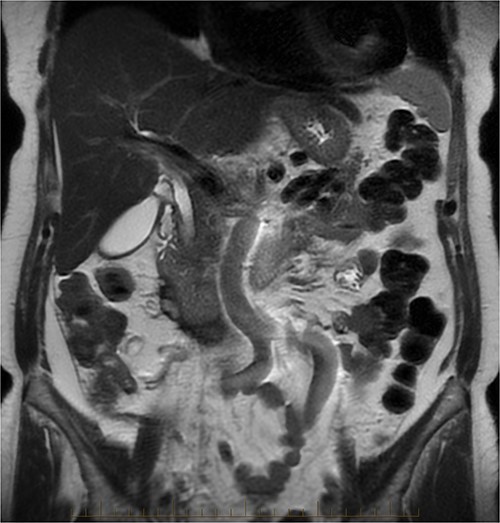

After further discussion with the reporting radiologist, a magnetic resonance imaging (MRI) was performed, which confirmed the presence of an acute periduodenal hematoma surrounding D2 and D3, lying in the retroperitoneal space, anterior to the right perirenal space. Etiology was uncertain. No abnormal enhancement within the bowel to suggest a bowel wall lesion or infiltrating mass (Figs 3 and 4).

MRI abdomen, coronal view. T2 hypointense, T1 iso to hyperintense material surrounding D2/D3 without enhancement in keeping with hemorrhage. No vascular or bowel wall lesion identified.